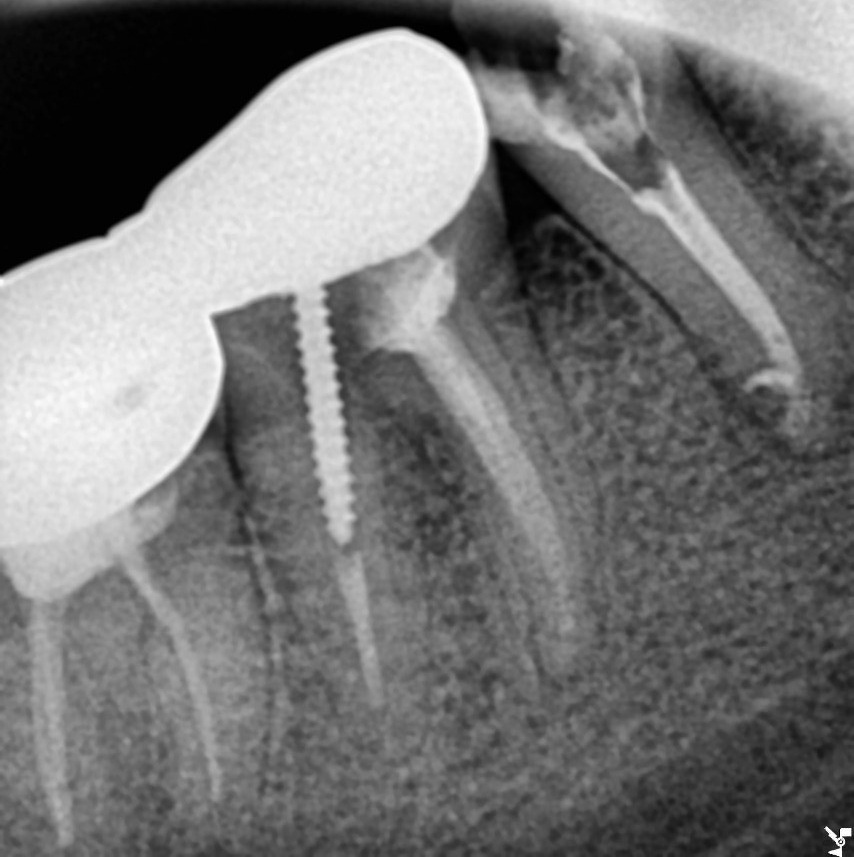

환자분께서도 내원 횟수가 많았지만 잘 도와주셨고, 여러 번 소독을 한 결과 통증도 줄어들었고

신경치료 마무리 날 운이 좋게도 부근관까지 약제가 충전이 되었네요.

처음에 미세하지만 흔들렸던 증상도 없어지셔서 원활한 저작을 위해 보철 치료도 이어서 진행해 드렸습니다^^